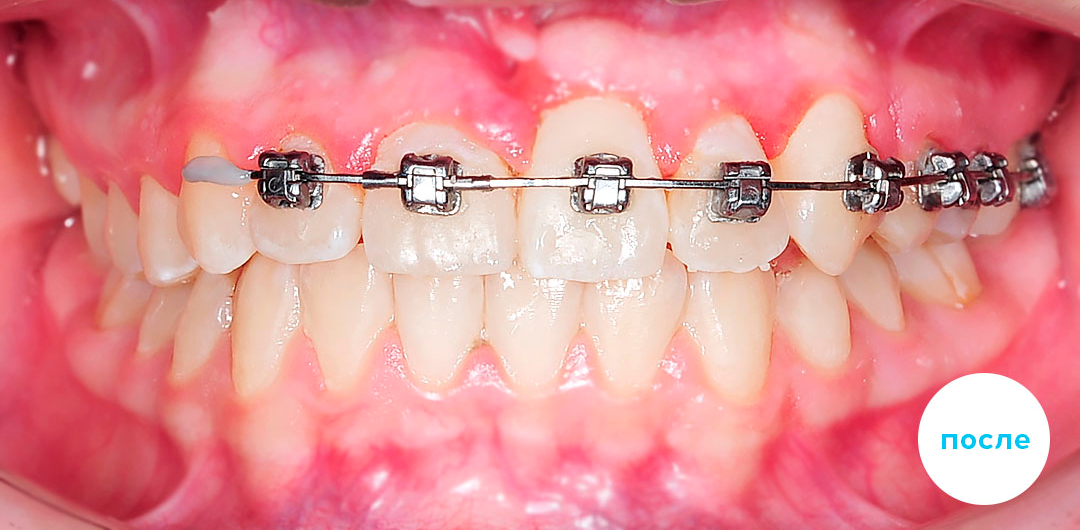

Работы специалиста